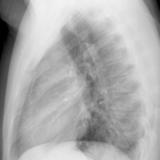

Case 9 Thymoma PA

Date: 04/04/2010

Views: 3182